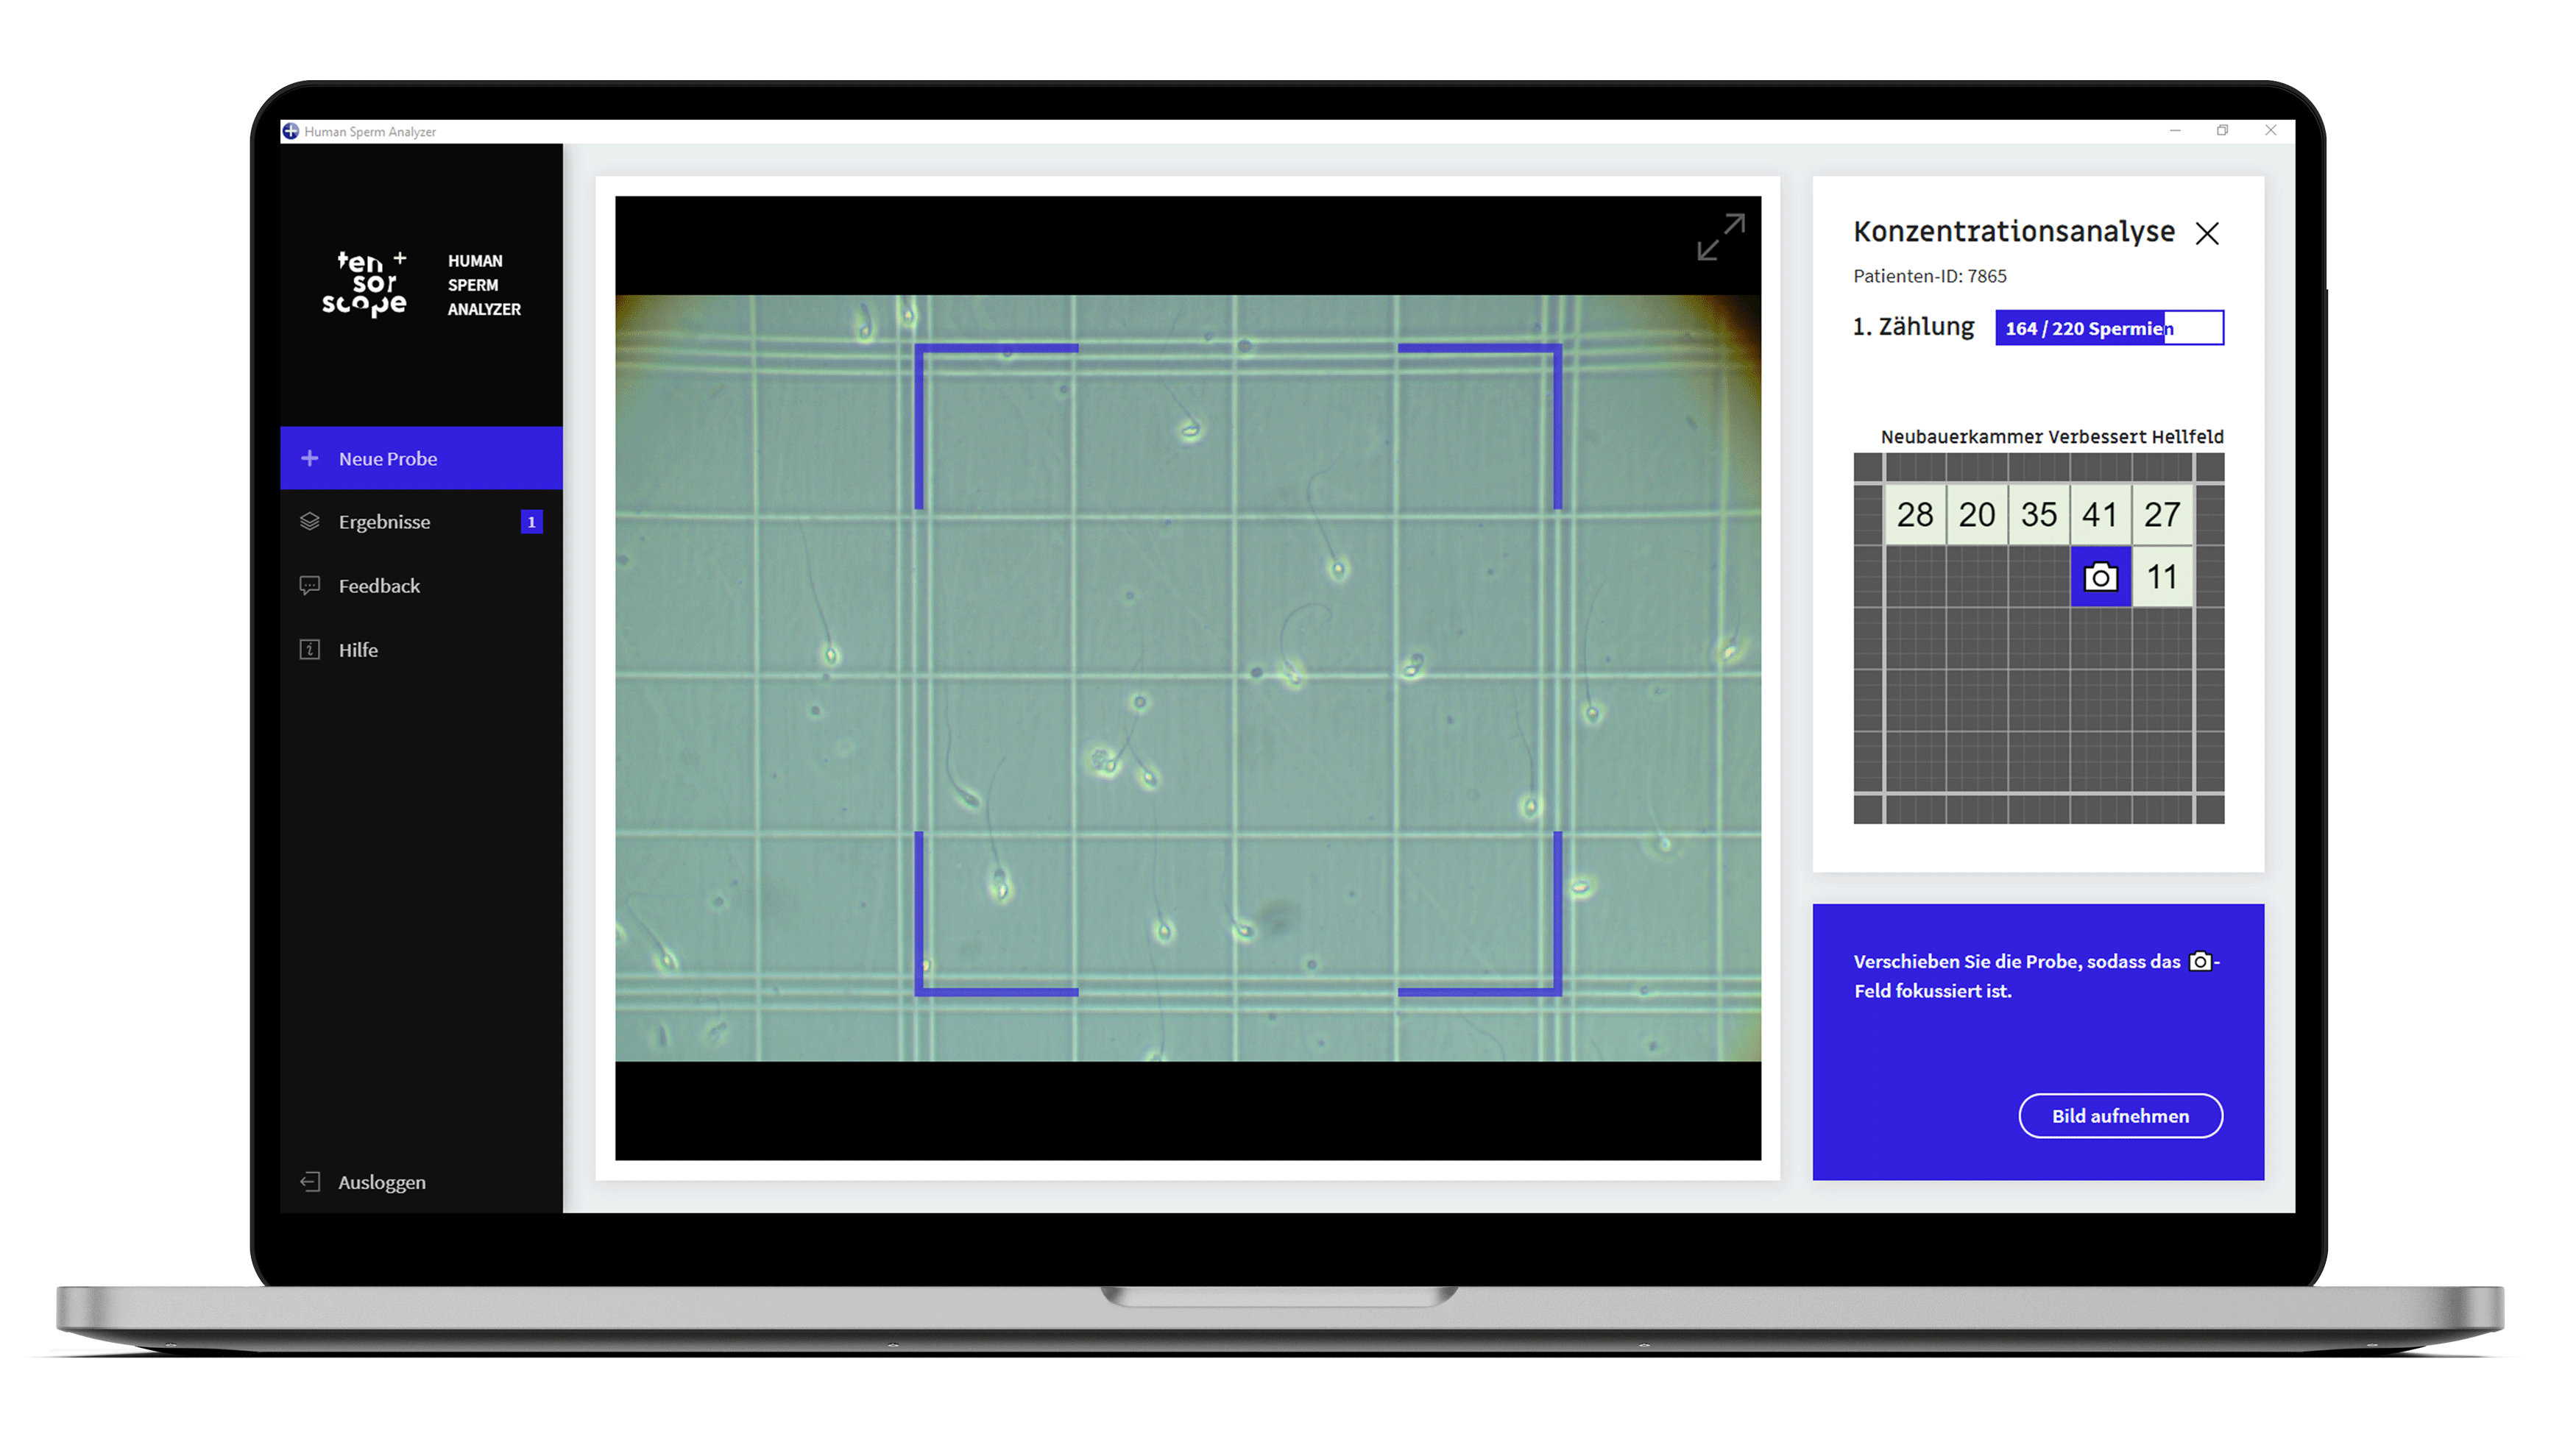

Anhand intelligenter Algorithmen ermöglicht unsere Software zur Spermiogrammanalyse die exakte automatische Bestimmung mikroskopischer Kennzahlen des männlichen Ejakulats: Konzentration, Motilität und bald auch Morphologie

Ãbersichtliche Darstellung der Ergebnisse in der App und als PDF.

Der kostenfreie Seminal Analyzer ist auf Windows-Geräten nutzbar. Verbunden mit einer Kamera und Ihrem Phasenkontrastmikroskop wird ihr Computer zu einem intelligenten Gerät für die Spermien Analyse.

Die tensorscope AI Algorithmen ermöglichen eine präzise Auszählung und Bestimmung von Spermien.

Der Seminal Analyzer übertrifft manuelle Auswertungsmethoden von Mikroskopanalysen an Effizienz und Genauigkeit